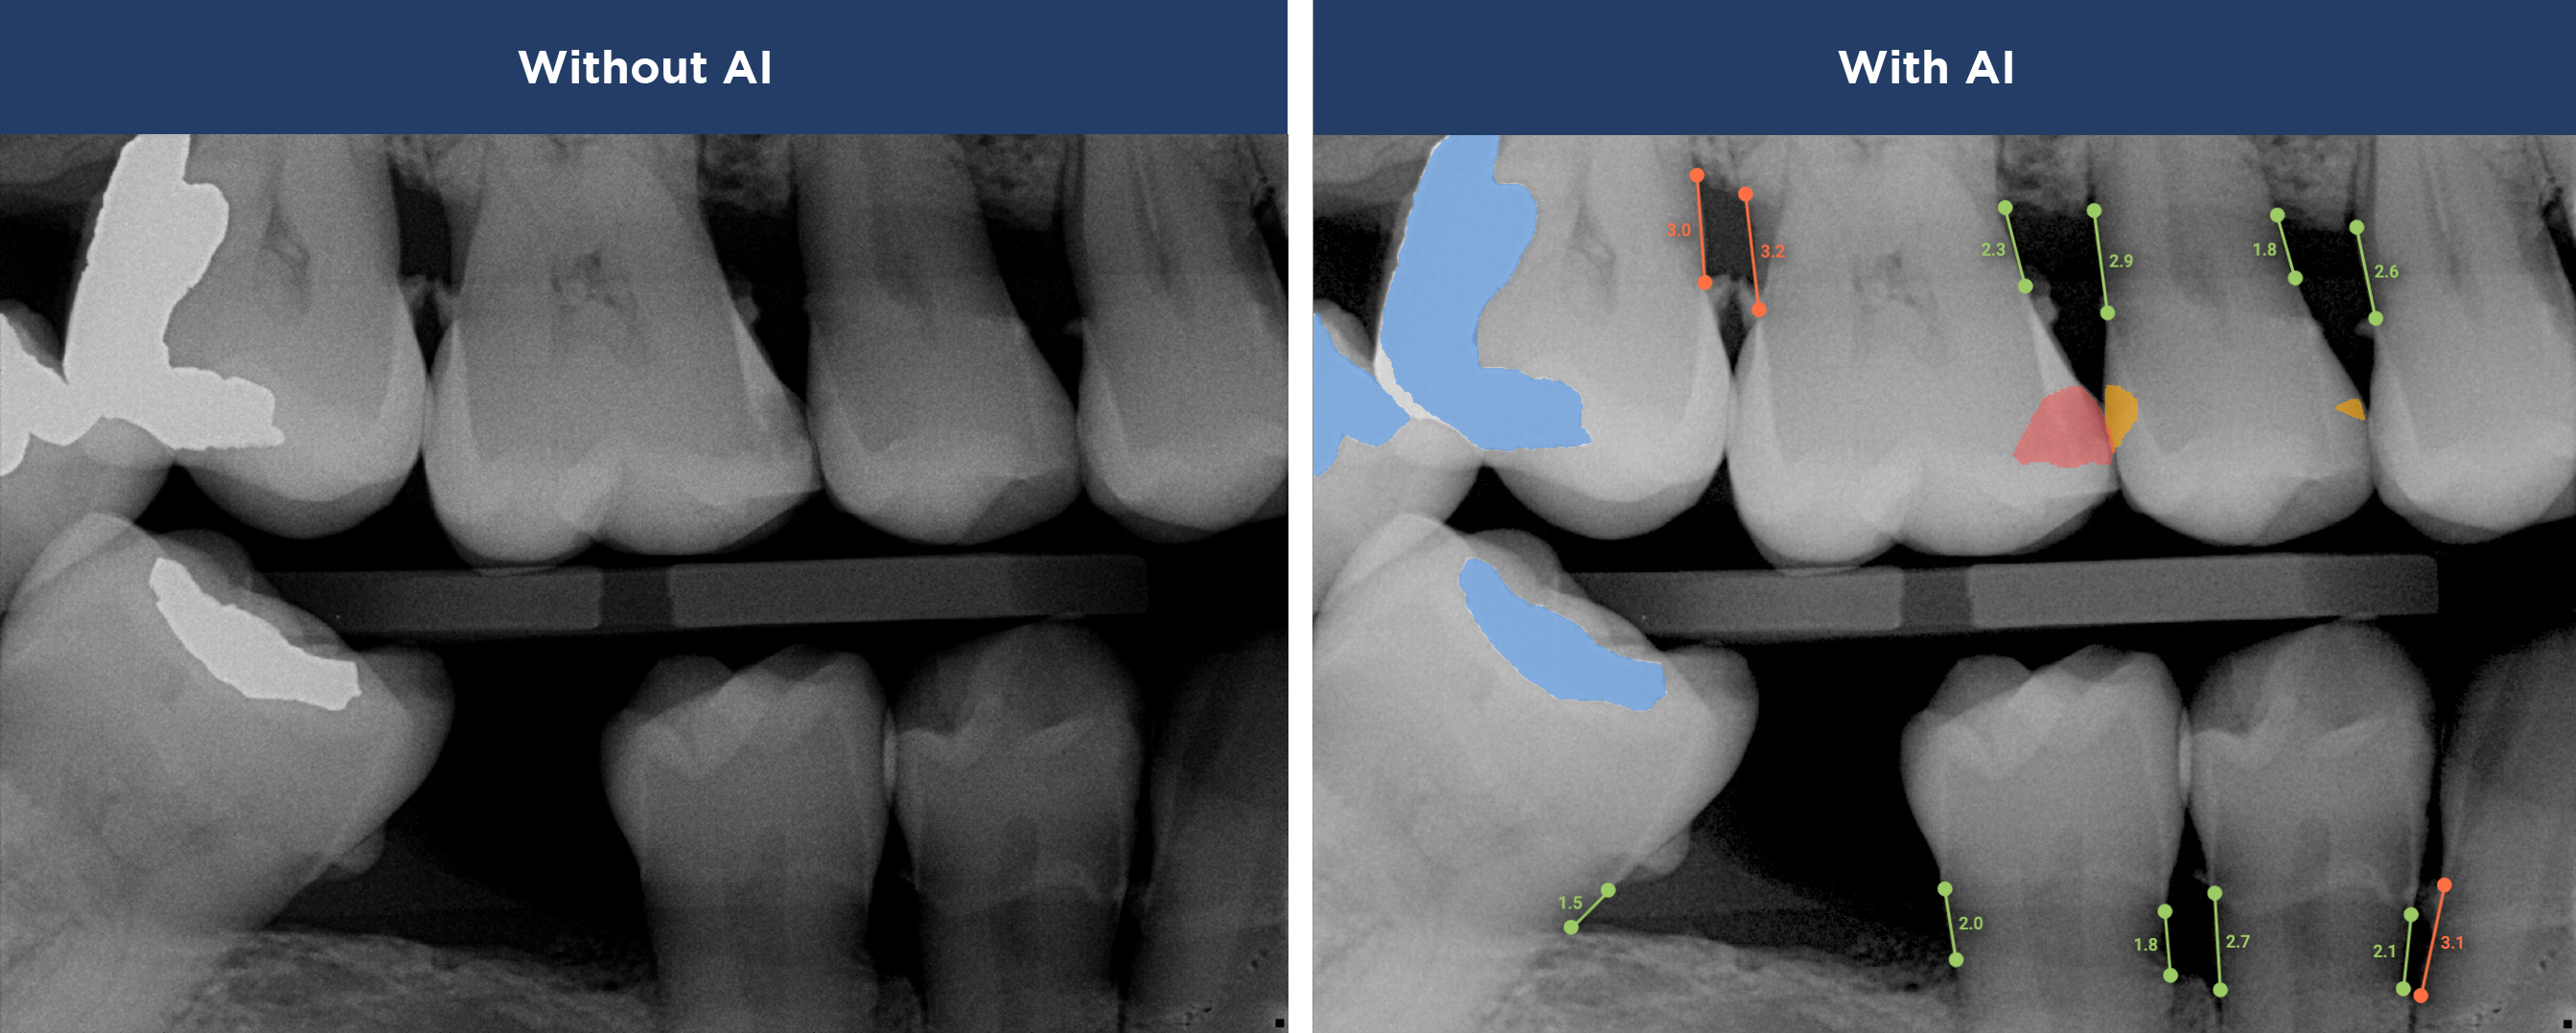

See More with AI

Where Advanced Technology Meets Personalized Care

Overjet AI's patient-centric technology combines human intelligence with the power of artificial intelligence.

Best in class dental care for every patient, on every visit.

Confidence in Your Diagnosis

Our practice is proud to provide the best technology in the dental industry, including Overjet AI for instant X-ray analysis.

Overjet’s artificial intelligence technology transforms traditional black-and-white X-rays by adding a layer of data that instantly outlines decay (cavities) and measures bone loss. This makes it easy for you to see your results alongside your dentist. It’s like getting a second opinion delivered instantly. With Overjet’s analysis and easy-to-read presentation, you will have the information you need to make an informed decision about your oral health. Together, we’ll review your findings and discuss the best steps to take to achieve your goals.